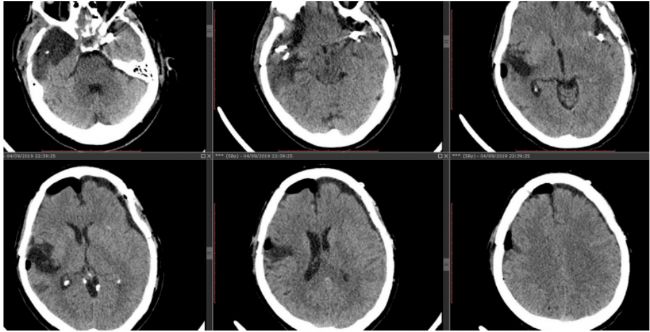

術前圖像

圖2:術前數(shù)字減影血管造影(DSA)顯示未破裂的動脈瘤和既往手術使用的動脈瘤夾。

圖像由巴西圣保羅聯(lián)邦大學(UNIFESP)血管神經(jīng)外科主任Chaddad博士(教授)提供。